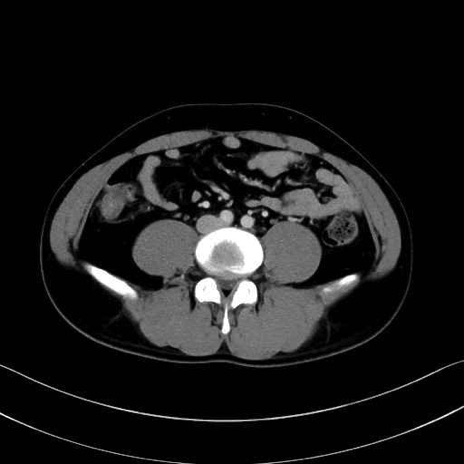

2. 腸腰筋群と骨盤底筋

大腰筋 (Psoas major)

腸骨筋 (Iliacus)